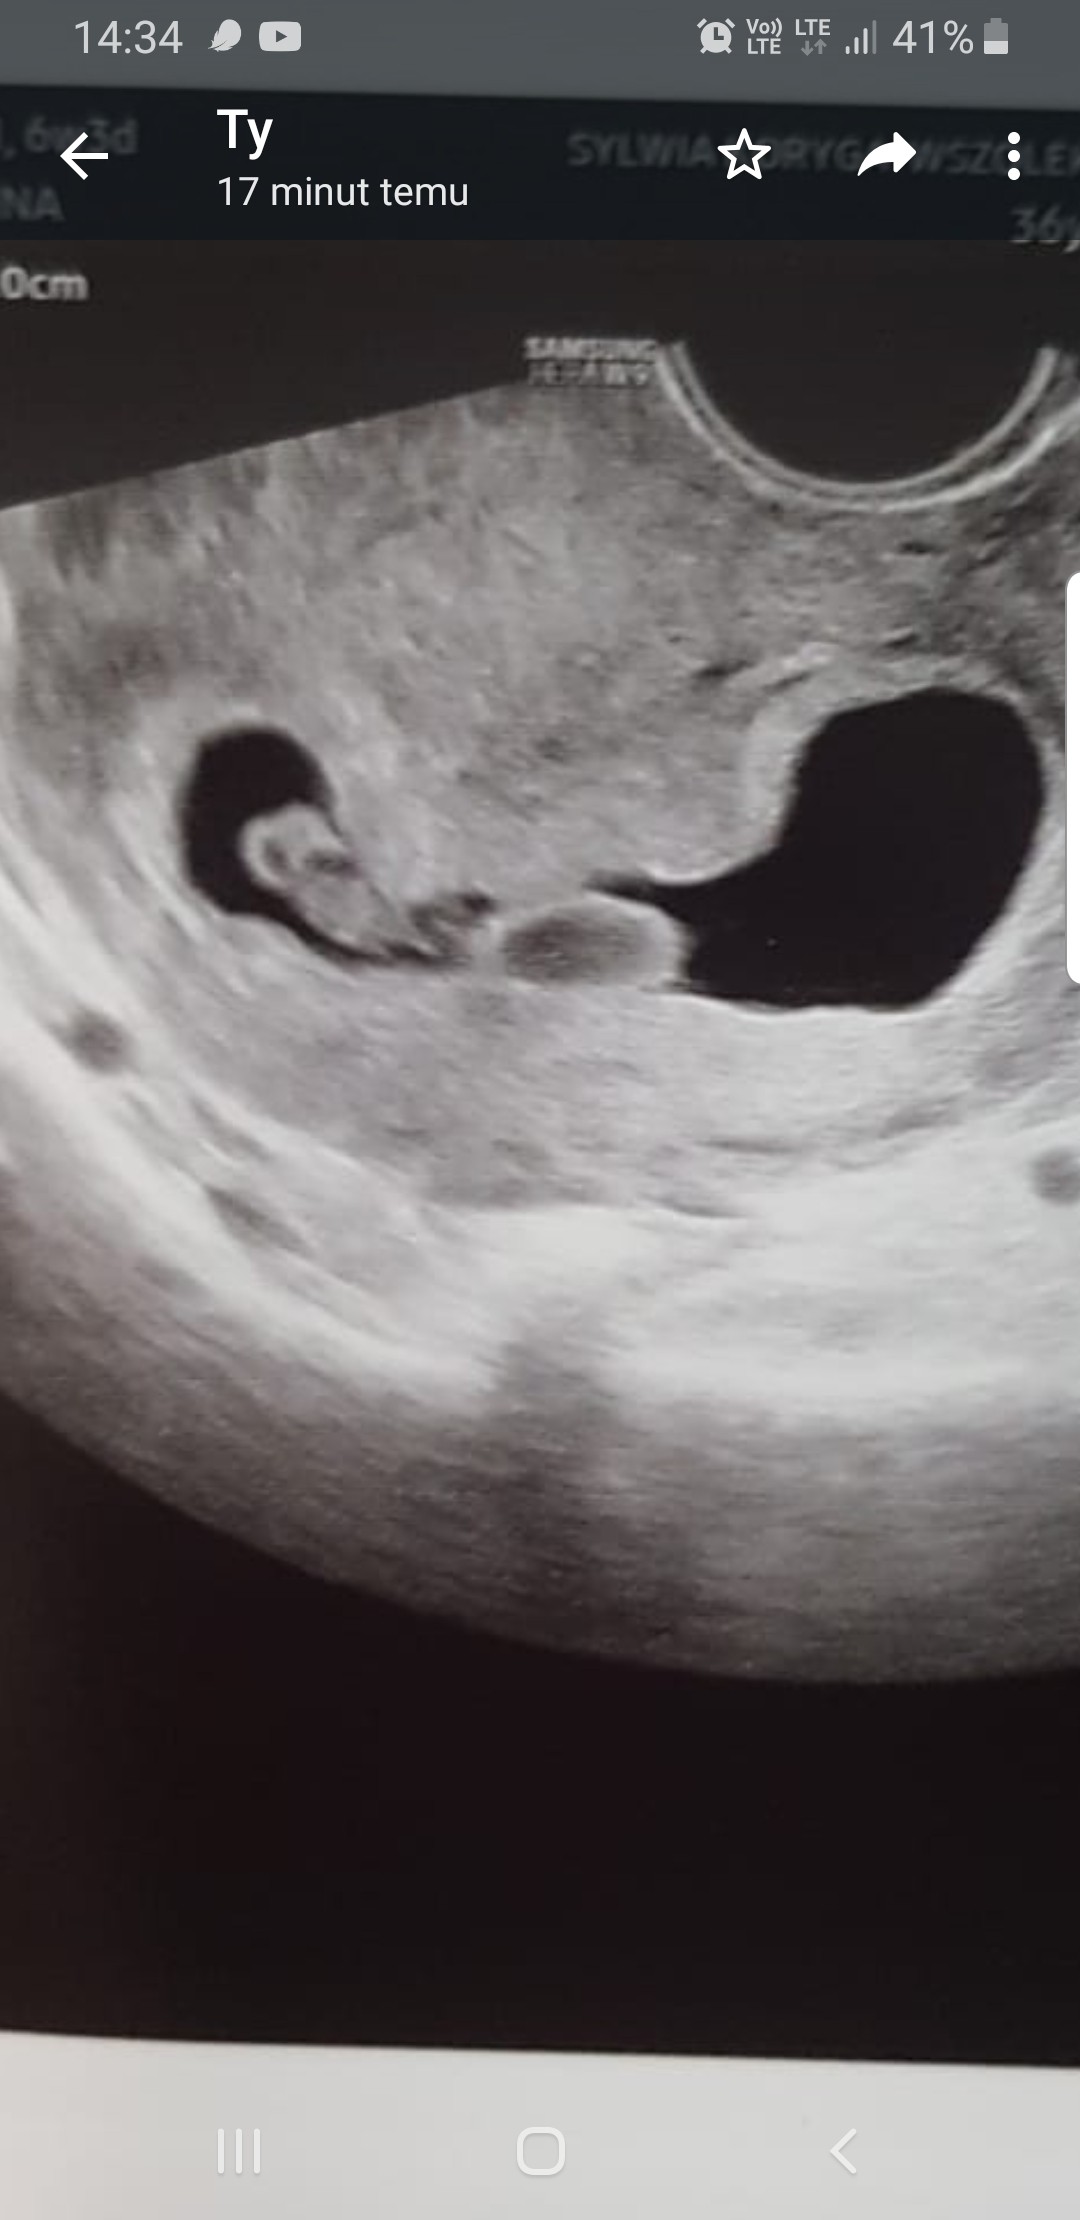

Właśnie poza tym że podejrzewa bliźniaki bo nie wie do końca co to jest to drugie to nie mówił nic. W pon było 7+1. Po Lewej zarodek z bijacym serduszkiem, po prawej to coś. Dzisiaj prof. Huras, jak on mi nie powie to nikt mi nie powie. Może się okaże że jednak to zwykła pojedyncza ciaza i odetchnę z ulgą. Oby do wizyty.

Załączniki

• Screenshot_20211115-143407_WhatsApp.jpg

Screenshot_20211115-143407_WhatsApp.jpg

169,5 KB · Wyświetleń: 69